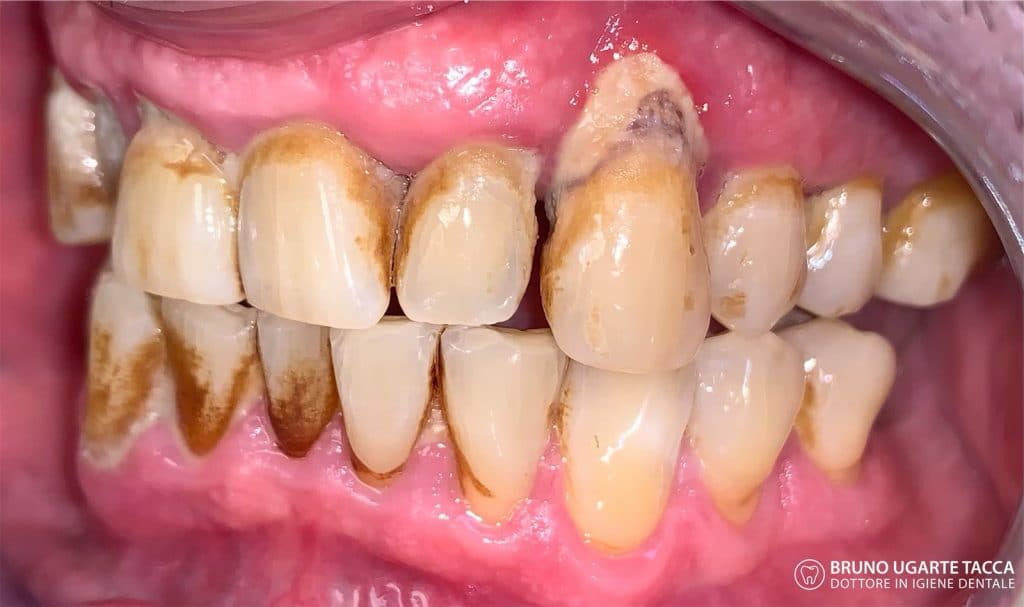

Performing the complete instrumentation

supragingival and subgingival with ultrasonic and / or manual instruments in one

single session or in two sessions at most performed over 2 days